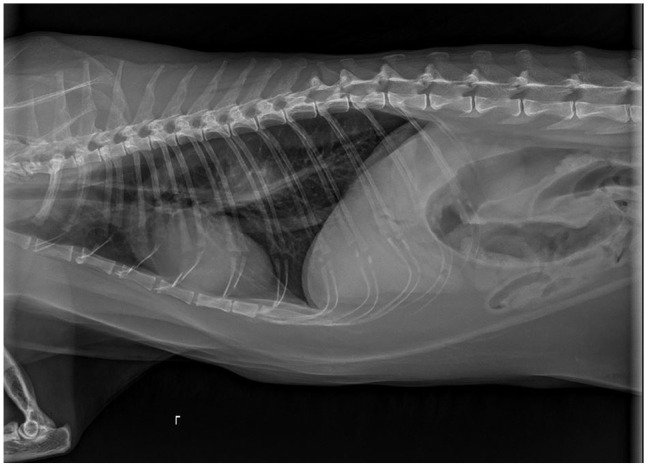

Case summary: A 15-year-old male castrated domestic shorthair cat was presented for acute lethargy, vomiting and hyporexia. Abdominal and thoracic radiographs revealed a caudal thoracic/esophageal soft tissue opacity with concern for an esophageal mass or an esophageal foreign body. Esophagoscopy confirmed the presence of a large, irregular, mid-esophageal mass. Laser ablation using esophagoscopy was utilized to debulk the mass. Approximately 80% of the mass was removed without complication and an esophagostomy feeding tube was placed. The cat was discharged the same day of the procedure. Histopathology and immunohistochemistry staining were consistent with a plasma cell tumor. Recheck esophagoscopy 2 weeks after the procedure revealed no evidence of regrowth and resolved clinical signs in the patient.